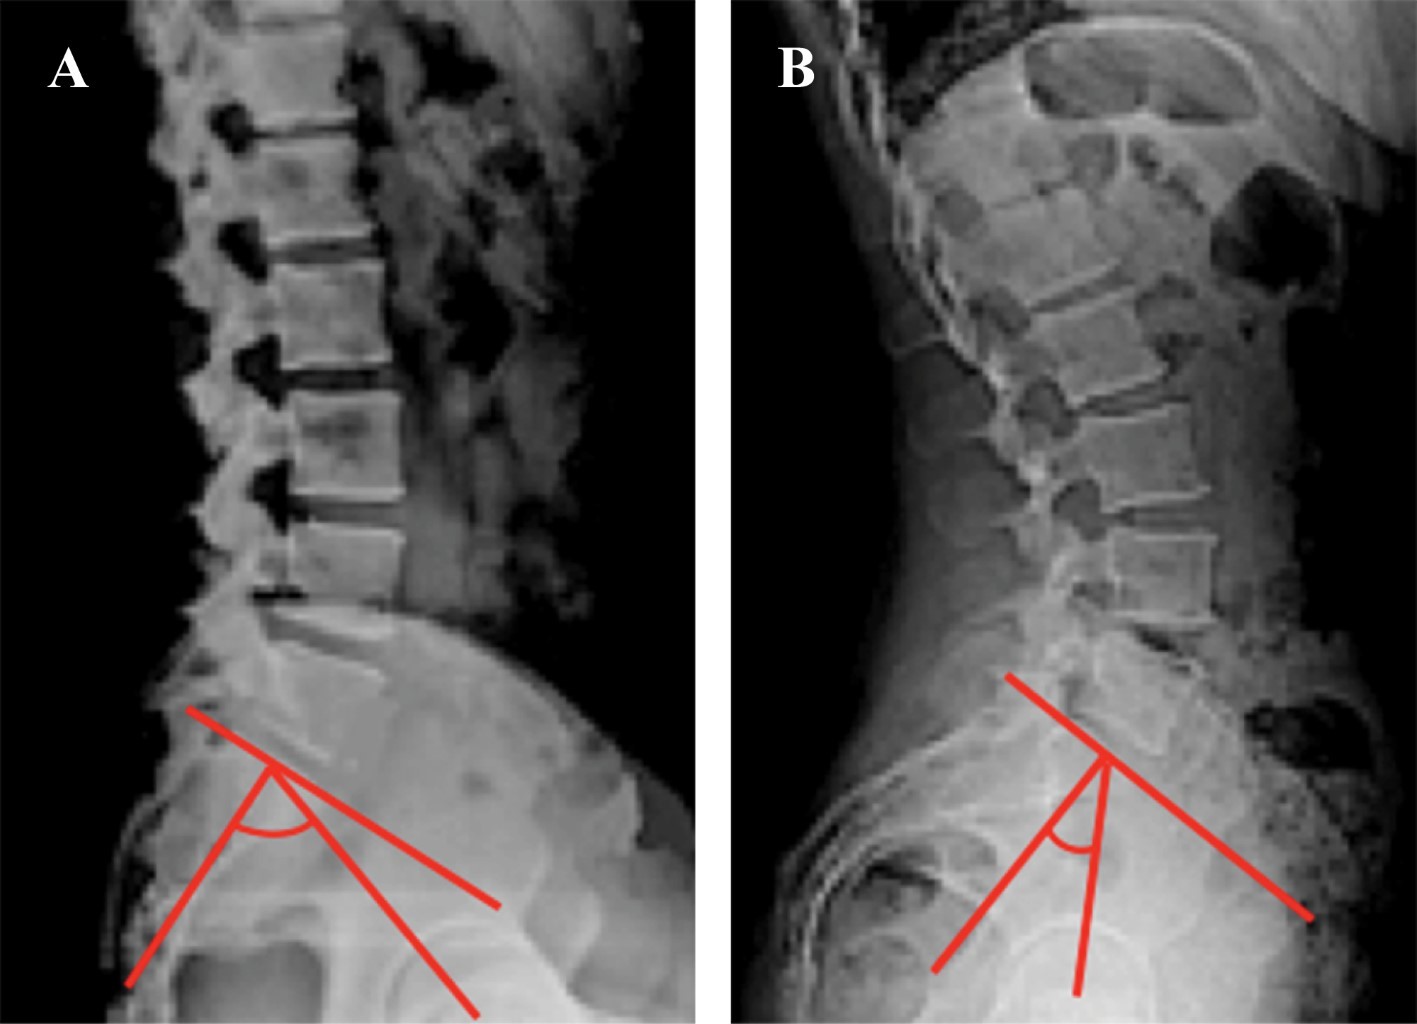

Inclinación pélvica (pelvis tilt). La definición de "pelvis tilt" está sujeta a una seria controversia. Los cirujanos de columna definen al "pelvis tilt" como el ángulo que forman el plano coronal y una línea dibujada desde el centro de las cabezas femorales (eje bicoxofemoral) al punto medio de la plataforma sacra (Figura 14A). Esta definición es útil en cirugía de columna, ya que se emplea para estudiar el balance sagital global atendiendo principalmente los centros de gravedad, tanto en columnas normales como patológicas. Lo anterior es de escasa utilidad en cirugía artroplástica de cadera cuando se estudia la posibilidad de luxación.

En cirugía de cadera se prefiere definir a la inclinación pélvica (pelvis tilt) tomando en cuenta la positividad o negatividad del ángulo formado entre plano anterior de la pelvis y la línea del plano coronal (Figura 14B). La razón de utilizar esta última definición es porque el interés de un cirujano artroplástico de cadera es la correcta colocación del componente protésico acetabular. Es importante considerarla ya que sabemos que la rotación pélvica modifica la anteversión acetabular.

Figura 14